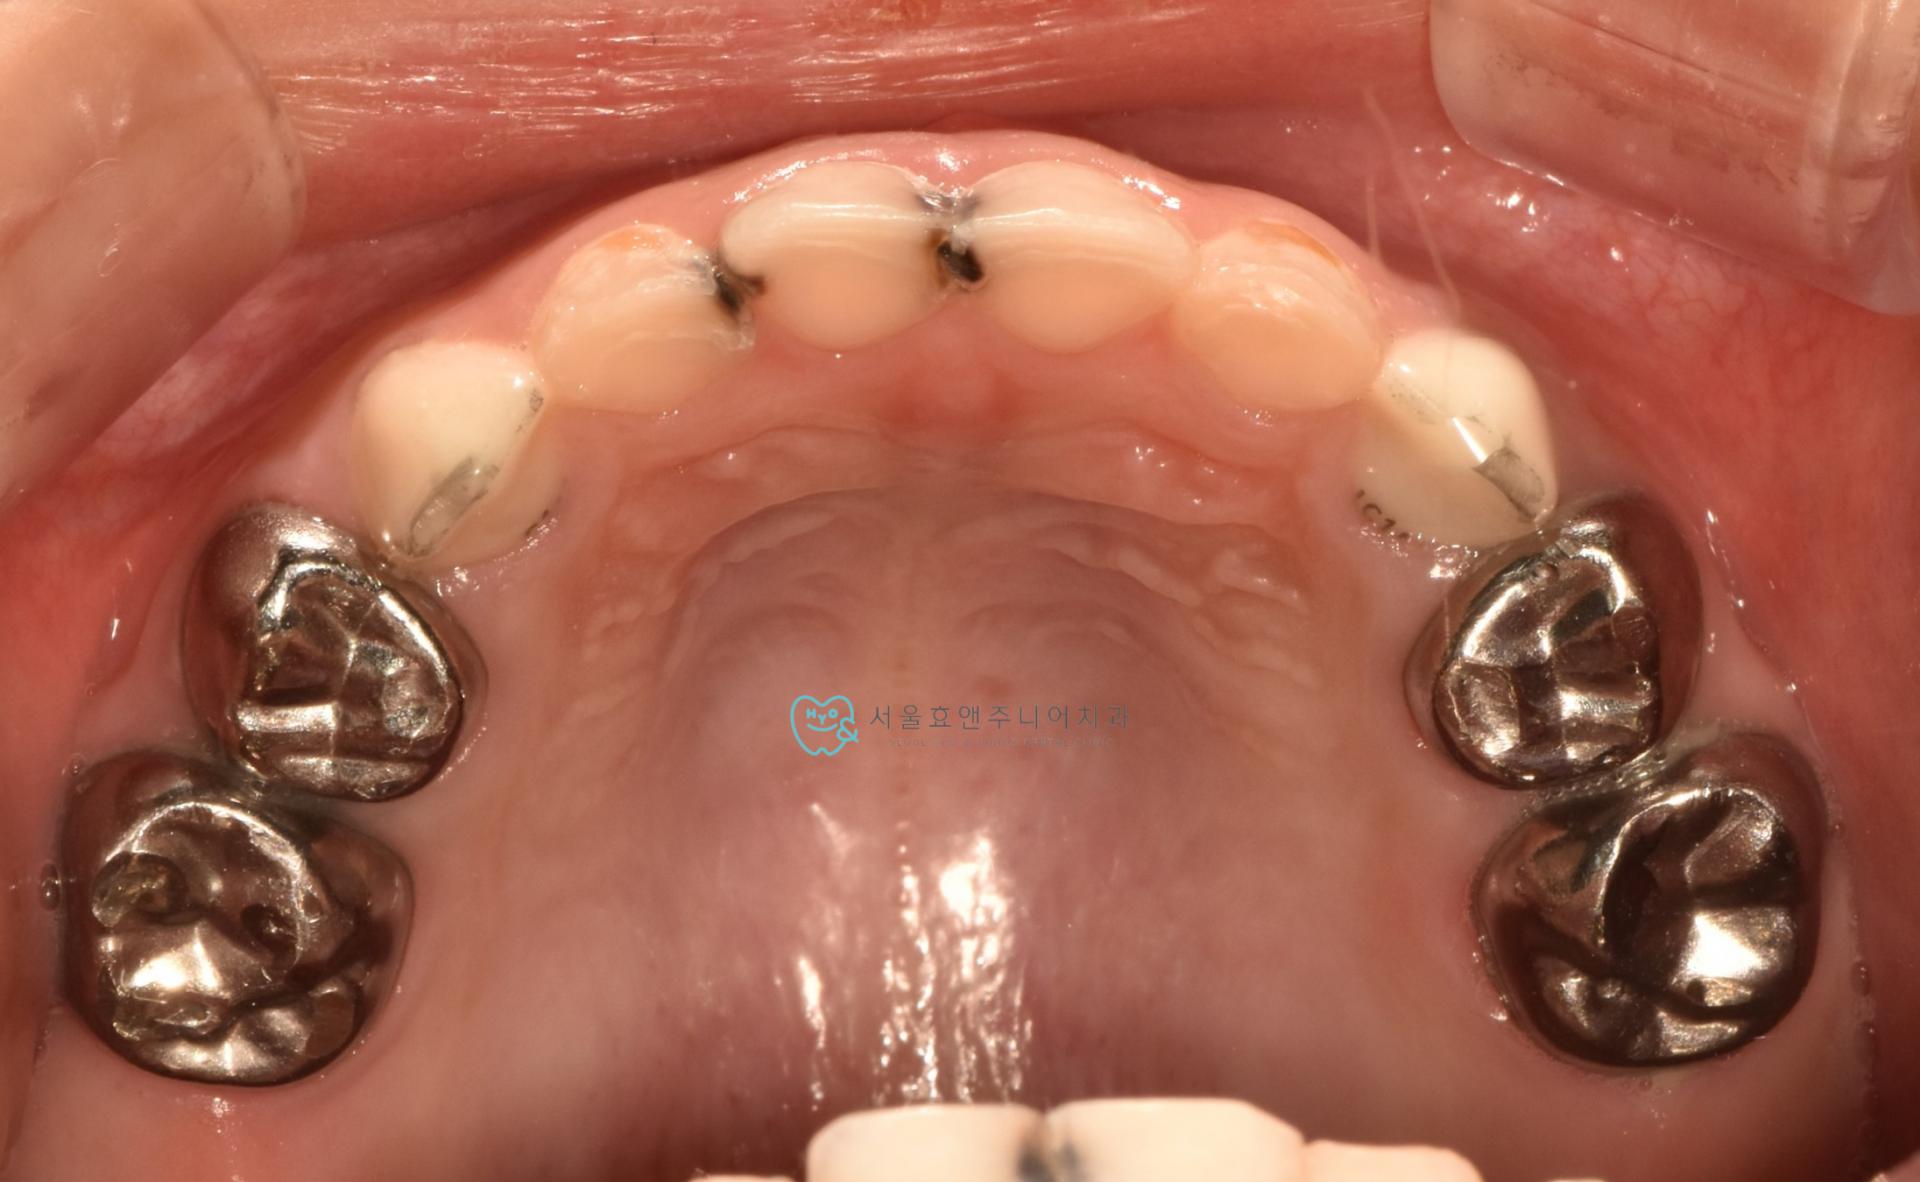

충치를 모두 제거한 뒤입니다. 여기저기 충치가 깊어 신경이 비치는 곳이 있습니다. 다행히 신경치료를 들어가야 하는 치아는 없었습니다.